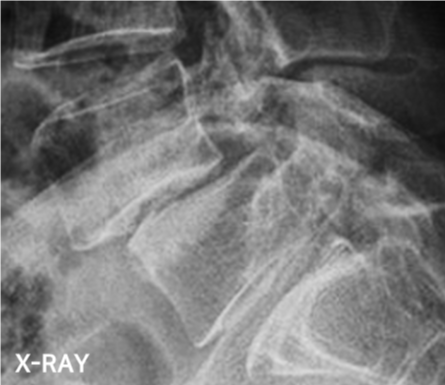

척추 전방전위증은 척추 분리증이 발전되거나, 퇴행성 관절 변화로 인해 중장년층에서 발생하는 경우가 많으며 척추뼈가 앞으로 이동해 신경을 압박하게 되고 하지 증상이 발생하게 됩니다.

진행되면 뼈가 이동하여 신경을 압박하게 되고, 척추협착증이 동반되어 다리에 증상을 일으키는 경우가 많습니다.

척추전방전위증 수술 전·후

2022.09.21

2022.12.30

ㆍ환자 동의를 받은 자료이며, 이미지 사진은 실물과 다를 수 있습니다.